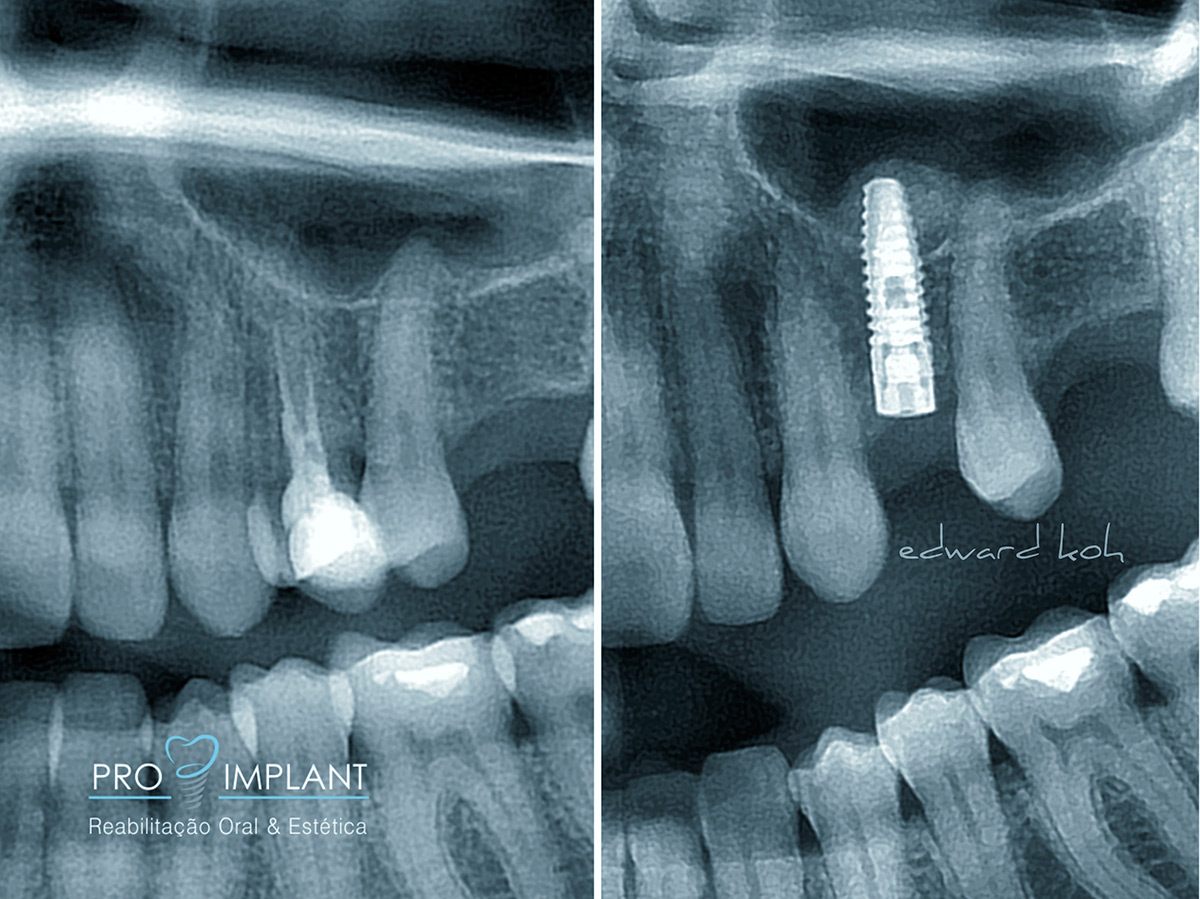

A perda de dentes pode levar a problemas estéticos, de oclusão (mordida) e perda óssea. Portanto é fundamental uma rápida reposição do elemento perdido. Os Implantes Dentários são parafusos de titânio que substituem a raiz dos dentes perdidos. O implante dental serve de apoio para a prótese (coroa) que deve ser semelhante aos dentes: naturais em estética e função. Os Implantes Dentários podem ser indicados para repor a perda de todos os dentes, de alguns ou de apenas um dente.

O Implante Dentário inibe a atrofia do osso após a perda de um dente; é fixo e não há necessidade de comprometer os dentes naturais adjacentes.